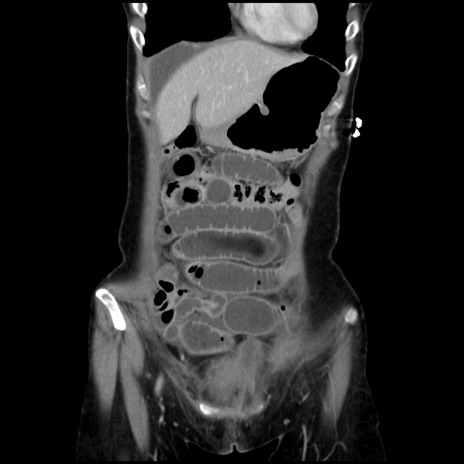

症例32(冠状断像)

【症例】40歳代 女性

【主訴】上腹部痛、嘔気・嘔吐

【現病歴】約9時間前頃から急に上腹部痛、嘔気、嘔吐が出現。改善しないため救急要請。

【既往歴】子宮頚癌(広汎子宮全摘術、放射線療法)、腸閉塞

【身体所見】腹部:平坦、軟、腸雑音亢進、上腹部を中心に腹部全体に圧痛あり。

【データ】WBC 8400、CRP 0.03